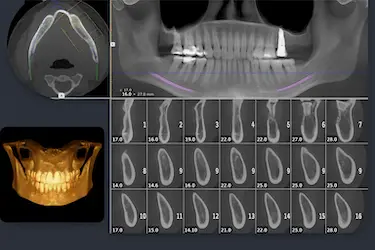

La principal ventaja de hacerse un TAC dental 3D es que permite a nuestros especialistas realizar cortes bidimensionales y tridimensionales de las imágenes obtenidas de tu boca.

Gracias a lo que se ve en una radiografía TAC 3D, el odontólogo pueden averiguar fácilmente:

- Cuál es la densidad y, en consecuencia, la calidad del hueso de la mandíbula.

- Dónde se encuentran los nervios y los vasos sanguíneos con total precisión.

- Qué piezas dentales y estructuras se encuentran en mal estado.

Estos datos aseguran a nuestros especialistas el diseño de un plan de tratamiento odontológico extremadamente preciso.

Mucho más que si solo contase con ortopantomografías, es decir, con radiografías panorámicas convencionales.

Con las fotos de un TAC dental se pueden ver imágenes detalladas de los dientes, huesos maxilares, mandíbula, raíces dentales y tejidos de alrededor, permitiendo un diagnóstico preciso.

Podemos clasificar diferentes tipos de TAC de la boca según la zona que se desea evaluar:

TAC mandibular

Se centra en la mandíbula, que es la parte inferior de la boca, donde se encuentran los dientes inferiores y las estructuras óseas relacionadas.

El análisis mandibular con TAC permite evitar riesgos durante la cirugía, ya que muestra la posición exacta del nervio dentario y las raíces de las muelas del juicio.

TAC de un solo diente o región específica

Se utiliza para examinar una pequeña área específica, como un solo diente o una sección limitada de la boca.

El TAC localizado es ideal cuando necesitamos estudiar un diente concreto antes de una endodoncia o valorar una pequeña lesión ósea sin exponer al paciente a más radiación de la necesaria.